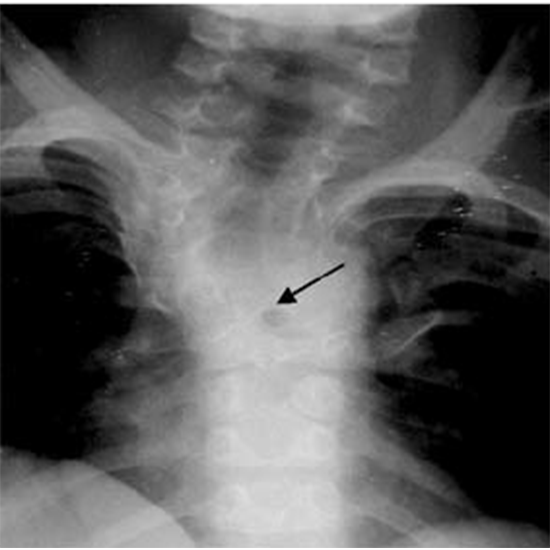

X-Ray Cervico Dorsal Spine is a radiography procedure that uses electromagnetic radiation for in-depth detection of cervical spine injury. The doctor recommends this procedure to detect the abnormalities, location of the fracture, and cause of pain as if the timely diagnosis is missed it can lead to severe neurological disorders.

Why is an X-Ray of Cervico Dorsal Spine Done?

Doctors recommend this procedure to assess the cervico-dorsal spine and detect underlying issues.